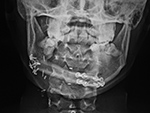

Mandibular reconstruction

25 year-old woman with mandibular osteosarcoma. The mandible was restored with autologous fibula free-flap reconstruction.